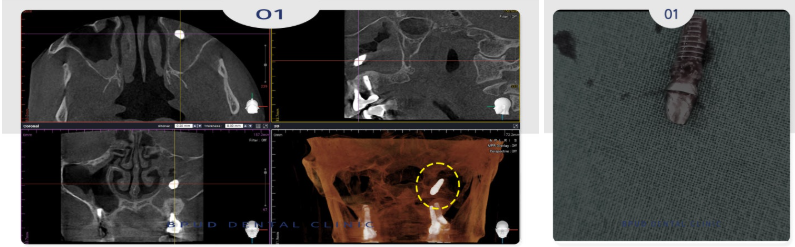

24.05.17

면밀한 진단을 위해 CT 촬영을 해보니

이미 상악동 내로 임플란트가 함입되어

있는 상태임이 명확하게 확인되었습니다.

환자분께서도 그렇게 들어간지 몰랐다고

하셨지만 코에서 냄새가 나고

콧물이 뒤로 넘어가는 증상은 있었다고 하셨는데.

상악동염도 심한 상태라

신속하게 안정적으로 제거를 완료하였습니다.